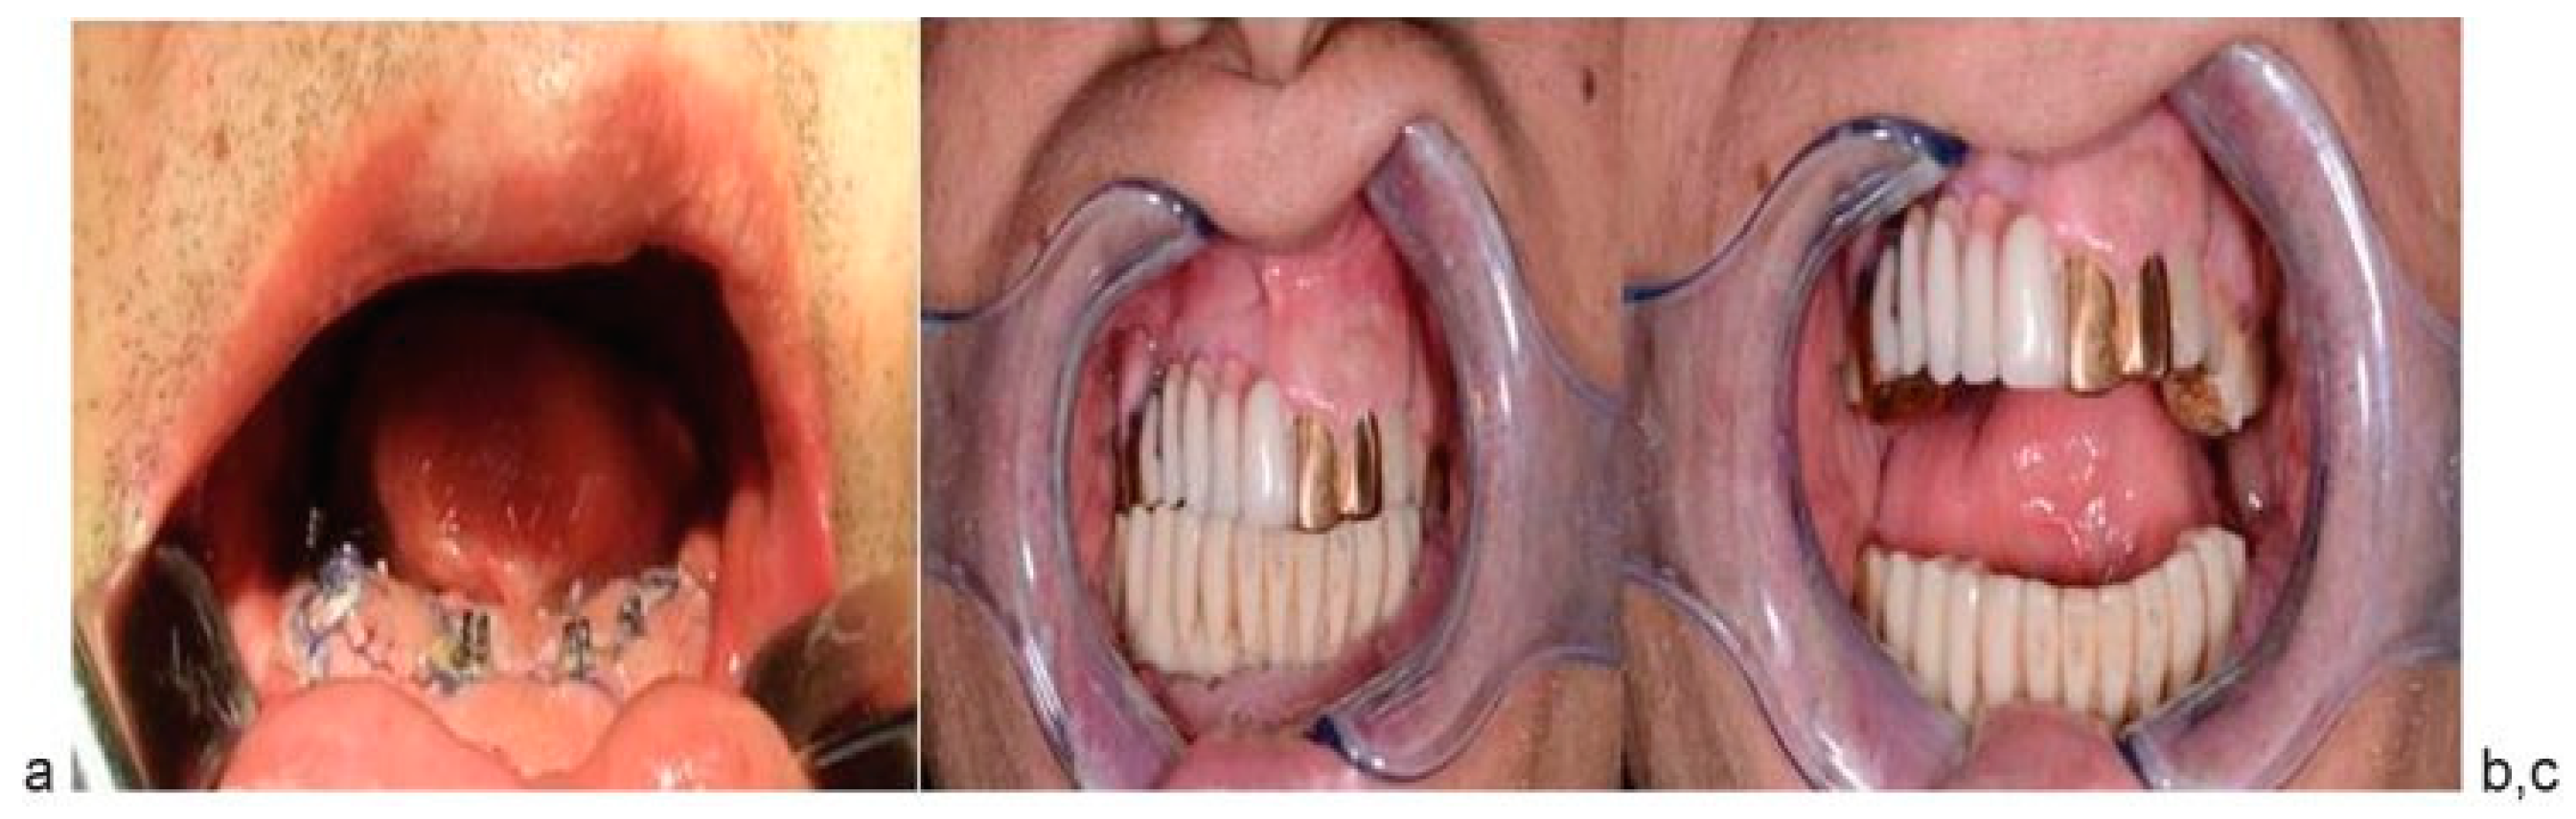

Orthopedic Step

The parallelism of six abutments was cheeked. Sterile and polished temporary bridge prosthesis was fixed on abutments (Figure 7a). Occlusion and mouth opening were checked (Figure 7b,c). Adaptation of orthopedic device in one step with surgical intervention allows achieving full value orthopedic rehabilitation in early postoperative period.

Three months later, after checking of osseous integration of dental implants, the final prosthesis was applied to one.

Figure 7. (ac) Orthopedic rehabilitation in early postoperative period.